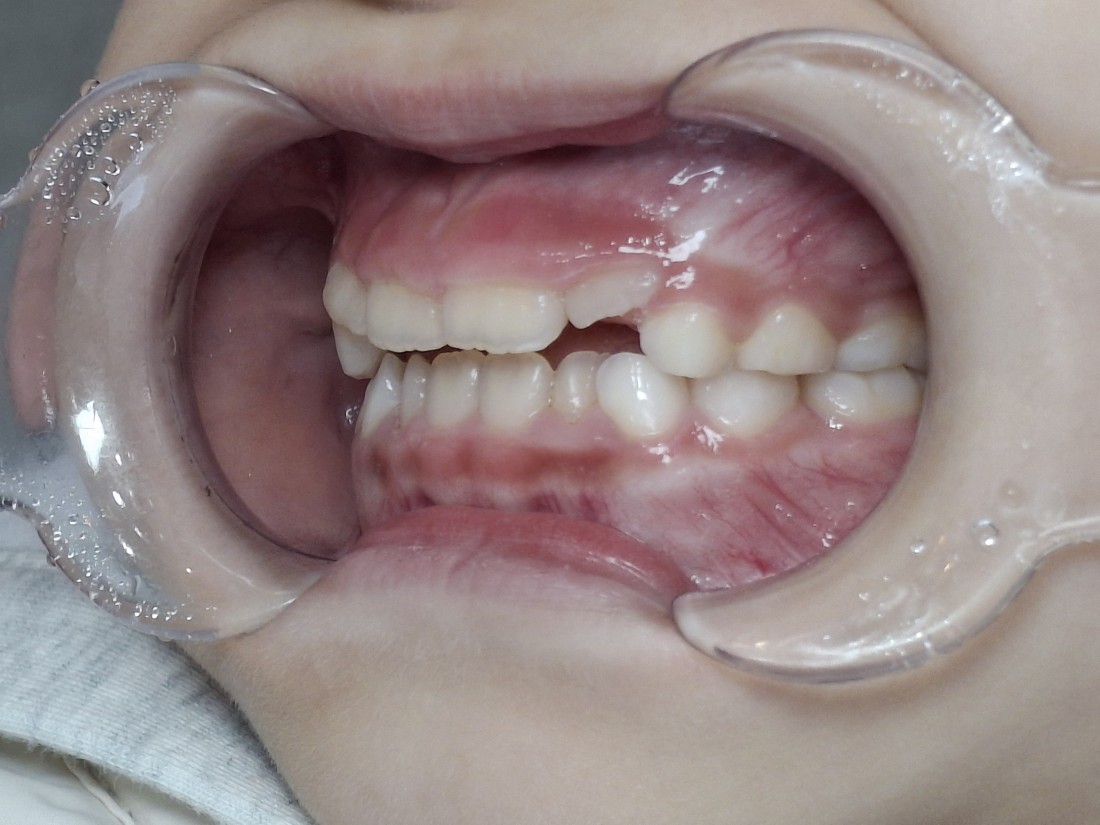

실제로 대한치과교정학회 치료지침 상

어린이 부정교합의 경우

턱 성장과 밀접한 관련이 있기 때문에

혼합치열기 (만5세~12세) 사이에

골든타임을 지켜

조기에 치료를 시작하는 것을

적극적으로 권장합니다.